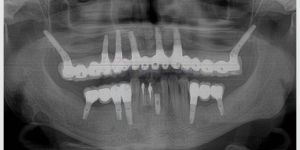

A evolução das técnicas de implantes dentários tem sido notável nos últimos anos, e uma das inovações mais significativas é o enxerto ósseo biomolecular. Este método revolucionário na medicina regenerativa proporciona uma integração mais eficaz entre o implante e o osso do paciente, otimizando os resultados e a durabilidade dos procedimentos. A Clínica ImplArt, com sua vasta experiência e mais de 10.000 casos de implantes dentarios realizados, destaca-se na aplicação desta tecnologia de ponta, beneficiando pacientes de todo o Brasil e do mundo.

Os enxertos ósseos biomoleculares têm mostrado resultados impressionantes em diversas frentes da medicina regenerativa. Sua aplicação tem se destacado particularmente na odontologia, onde médicos e pacientes têm observado um sucesso clínico notável.

Diversos estudos de caso demonstram a eficácia e os avanços biomédicos associados a essa tecnologia. Pesquisas conduzidas por renomadas instituições, como a USP e a UNESP, apresentaram resultados que comprovam a eficácia do enxerto ósseo biomolecular na integração entre implantes dentários e os tecidos ósseos dos pacientes.

Aumento de densidade óssea em pacientes com perda óssea | USP | 80% de sucesso com regeneração total |

Implantes dentários com enxerto ósseo biomolecular | UNESP | 95% de taxa de sucesso após 1 ano |